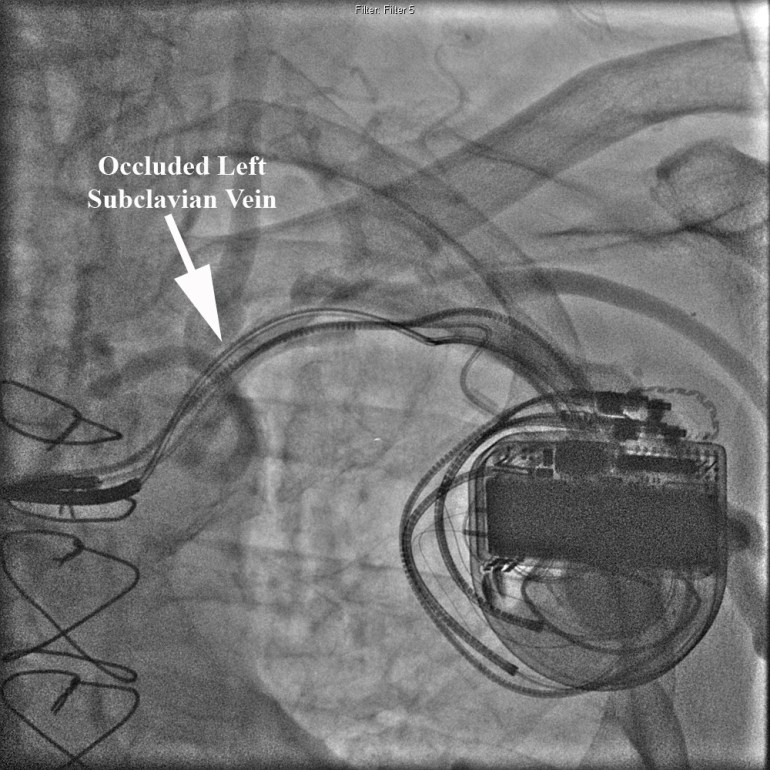

He was scheduled for upgrade of his defibrillator to a biventricular defibrillator with the addition of a left ventricular (LV) lead placed percutaneously in his coronary sinus. Of note, his initial right ventricular ICD lead (Medtronic Sprint Fidelis) had to be replaced several years ago. His in-situ ICD still had battery life and the decision was made to assess coronary sinus and left subclavian patiency prior to opening the ICD incision and risking device infection. Peripheral venogram of his left upper extremity revealed an occluded left subclavian vein in the midline (see Figure).